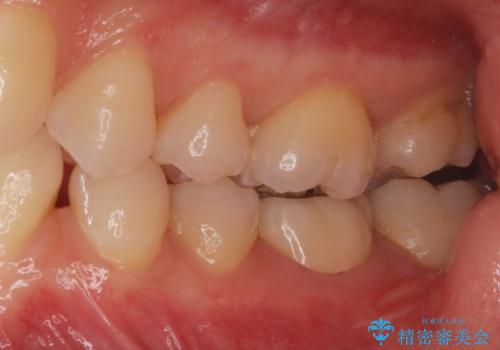

白い被せ物を入れたい。

- 他院で根管治療を終えて被せ物を入れたいとの事で来院。

形を整えて型取りをし、ジルコニアクラウンを装着しました。

被せ物が入りました。

根管治療が終わった歯は被せ物を装着しないと細菌が根管内に侵入し根の再発のリスクが増えるため早急に被せ物を入れる事をお勧めします。